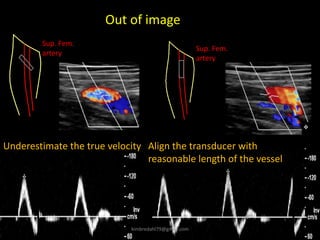

Sup. Fem.

artery

Underestimate the true velocity Align the transducer with

reasonable length of the vessel

Out of image